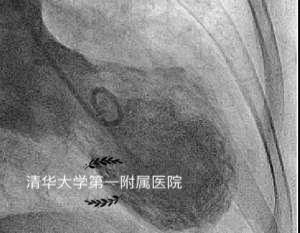

2年前,一名56岁的女性因为“突发胸痛3小时”就诊。入院前3小时患者与家人生气争吵后突发胸痛,伴黑曚、气促及后背部不适,遂就诊于清华大学第一附属医院急诊科。急诊心电图大致正常,但心肌酶谱却明显升高,诊断考虑急性非ST段抬高型心肌梗死。第一时间的急诊冠脉造影却没有见到血管堵塞,于是进一步做了左心室造影发现心尖部呈气球样扩张。次日行心脏彩超也提示心功能受损表现。入院监测心肌酶峰值出现于发病20h,CK-MB12.76ng/mL、*NTT**0.290ng/mL,同时NT-pro-BNP升高2482ng/L(心衰指标)。诊断应激性心肌病成立,后续给予曲美他嗪口服,磷酸肌酸钠、复合辅酶营养心肌等治疗。1周后复查心脏彩超及心肌核磁心脏功能都恢复了正常。

急诊造影收缩期心脏呈球形